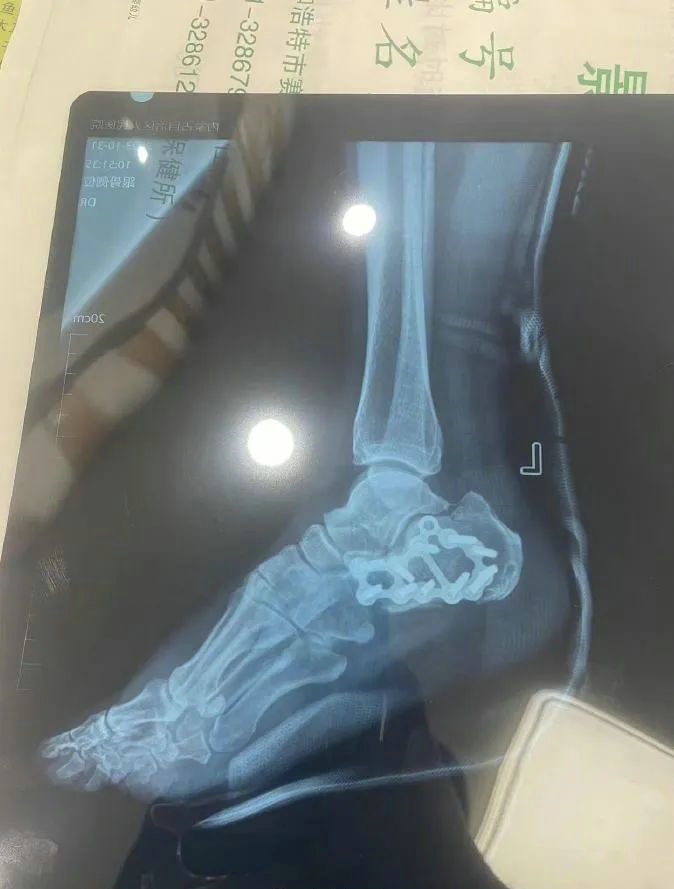

“那時(shí)候我剛工作了兩天,在第三天10月22日下午施工過(guò)程中從三層高的鐵架上摔了下來(lái),導(dǎo)致30厘米左右的鋼筋刺穿我的右側(cè)臀部,左腳跟也粉碎性骨折,被送往內(nèi)蒙古自治區(qū)人民醫(yī)院救治,當(dāng)晚做了手術(shù)取出刺在右臀部的鋼筋,10月30日又進(jìn)行了左腳粉碎性骨折手術(shù)?!崩紫壬嬖V記者。

據(jù)雷先生介紹,當(dāng)時(shí)內(nèi)蒙古騰龍建設(shè)工程有限公司許經(jīng)理問(wèn)過(guò)他賠付10萬(wàn)元能否解決問(wèn)題,他認(rèn)為這樣不太妥當(dāng)?!耙?yàn)槲业淖竽_骨折還要進(jìn)行二次手術(shù),并且我臀部受傷不能坐著,只能包車(chē)回家,會(huì)產(chǎn)生一系列的費(fèi)用。”雷先生說(shuō)。